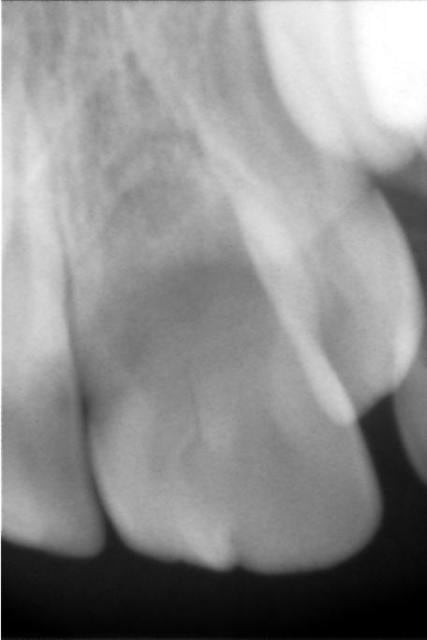

quitte a paraitre déphasé, une simple retro alveolaire, bien de face et montrant bien la racine m'irait bien, ce n'est pas une critique, ton truc est bien exposé

dans ta belle presentation du cas je trouve que ça me manque un peu, on ne voit pas l'anatomie de cette racine, on la devine mais tres mal, pourtant je trouve que c'est un élément primordial

La rétro se trouve dans le 2ème message (Cham2 jpg)